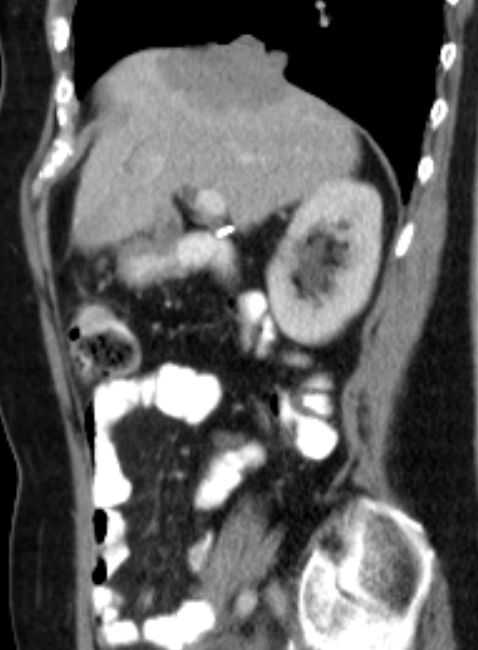

76-jährige Frau, die vor 13 Jahren ein Ovarial-Karzinom pT3b pNo Mo Lo Vo G2 hatte. Radikale OP, 6x Taxol - Carboplatin. Jetzt Lebermetastasen, RF linker Adnexbereich.